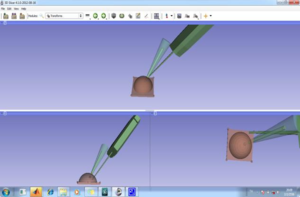

- 4.24 On the Design and Development of A Breast Biopsy Navigation System: Path Generation Algorithm and System with Its GUI Evaluation